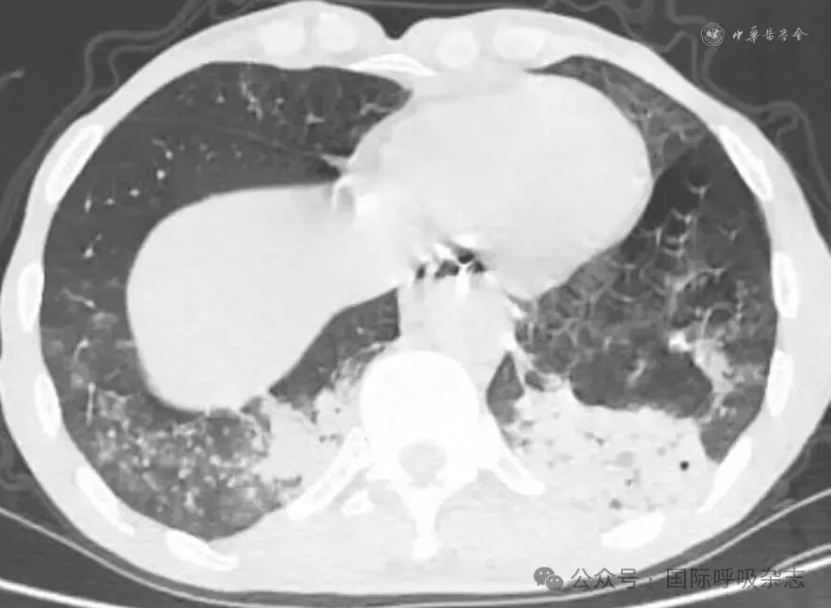

患者男,61岁,因“食管癌术后3年,咳嗽、气喘半年”于2025年3月14日入院。患者于2022年确诊食管鳞癌,曾接受新辅助免疫联合化疗、食管癌根治术、术后辅助免疫治疗、局部放疗及多线化疗等规范治疗。2024年12月经胃镜检查确诊为“气管食管瘘”,遂行空肠营养管置入术(图1)。后因咳嗽、气喘症状持续,辗转多家医院治疗效果不佳就诊于西安市胸科医院。入院查体:端坐呼吸,声音嘶哑,双肺可闻及湿性啰音及喘鸣音。实验室检查示炎症指标升高:白细胞计数8.82×109/L,中性粒细胞比例88.8%,C反应蛋白165.88 mg/L。血气分析pH值7.435,PaCO2为45.2 mmHg(1 mmHg=0.133 kPa),PaO2为55 mmHg,氧合指数200 mmHg,提示Ⅰ型呼吸衰竭。胸部CT提示气管食管瘘,伴双下肺感染及实变(图2)。支气管镜下见气管中下段膜部菜花样新生物,新生物下方可见瘘口(图3)。

图2:61岁男性气管食管瘘患者胸部CT(2025年3月14日)示气管食管瘘,双肺下叶感染、实变